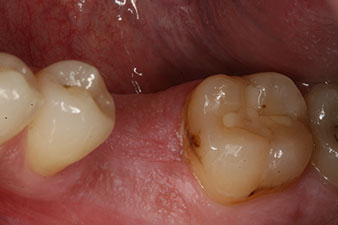

conformación

Figura 8: Se realiza la conformación para la corona definitiva.

Con ello, fue posible documentar una correcta osteointegración y una estabilidad biológica suficiente, lo que permitió realizar una conformación en la misma sesión.

Las figuras finales muestran la corona de composite monolítica atornillada in situ y la radiografía de control (figuras 9 y 10) (6).